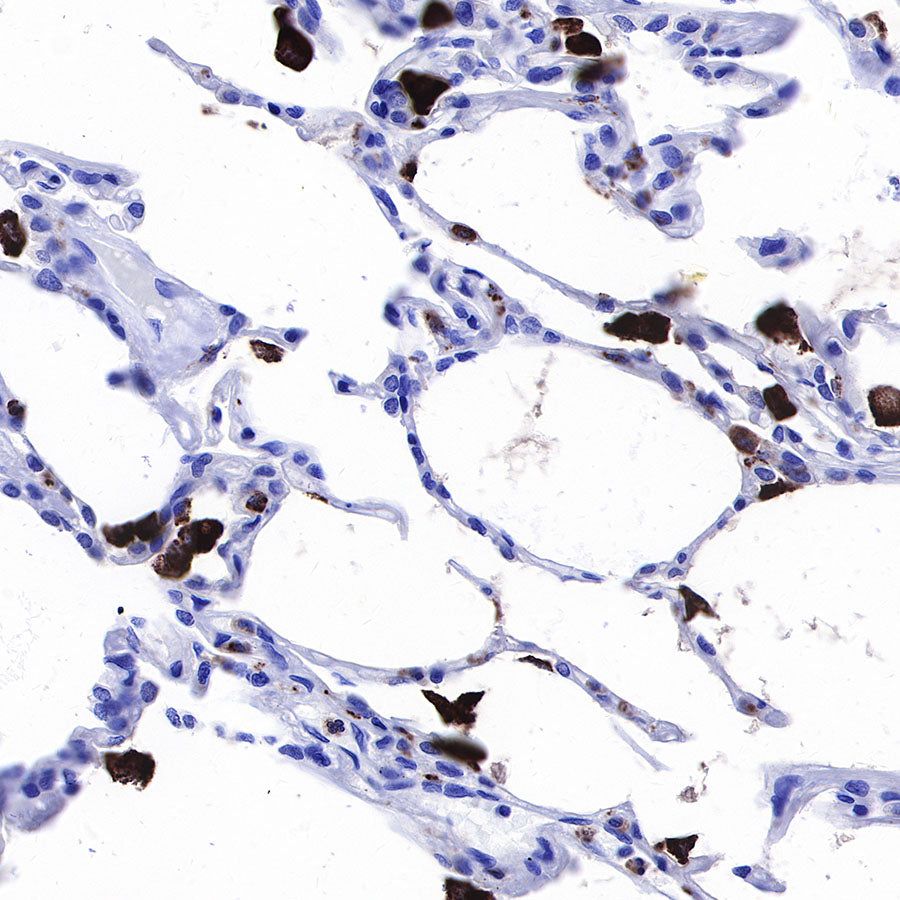

IHC shows positive staining in paraffin-embedded human lung. Anti-CD68 antibody was used at 1/1000 dilution, followed by a HRP Polymer for Mouse & Rabbit IgG (ready to use). Counterstained with hematoxylin. Heat mediated antigen retrieval with Tris/EDTA buffer pH9.0 was performed before commencing with IHC staining protocol.